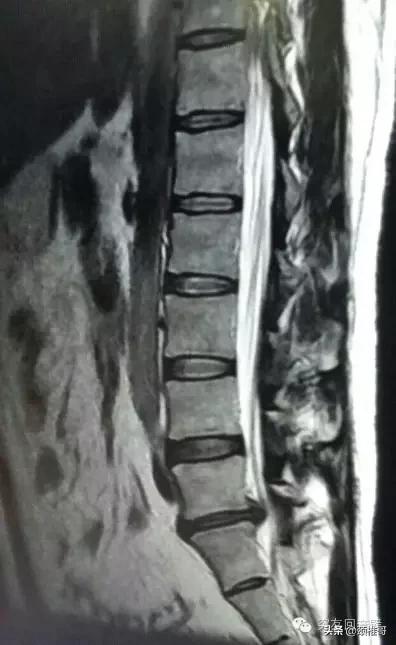

10月22日我再次做了核磁检查,诊断结果是“L5/S1椎间盘突出(向左后方型),硬膜囊受压,左侧椎间孔变窄”。27日上午,我在全麻下做了L5/S1椎间孔镜手术,术后所有症状都消失了,心里万分高兴。

图1:2014年10月22日核磁影像资料